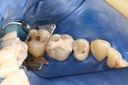

Gary Umeda #3 - 4 prep